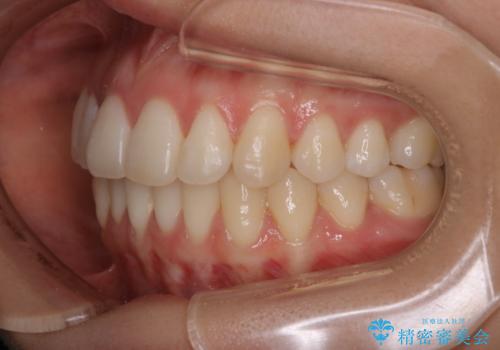

非抜歯でも劇的変化 インビザライン矯正治療

- 前歯のガタつきと噛み合わせの改善を主訴に初診来院され、審査の結果マウスピース装置による非抜歯での矯正を行うこととなりました。

元々の顎骨や口腔・歯槽骨が小さく、どうしても歯が並びきらない状況になっていました。マイクロインプラントという固定源からゴムかけを行うなど、補助装置を活用しながら臼歯部を順番に遠心方向(奥)に移動させていくことで抜歯をしなくても歯が並ぶよう計画を立てました。

歯のガタつきを治すため矯正治療を希望。審査の結果、非抜歯での矯正が可能であるという見通しが立ったためインビザラインによる非抜歯矯正治療を行った。

歯を並べるスペースを作るために、歯の遠心移動と歯列の拡大、歯自体を少しだけ小さく削る(IPR)という方法を複合的に組み合わせて配列を行いました。遠心移動用のゴムかけにはマイクロインプラントという小さいネジを用いて骨に直接固定源を求めました。